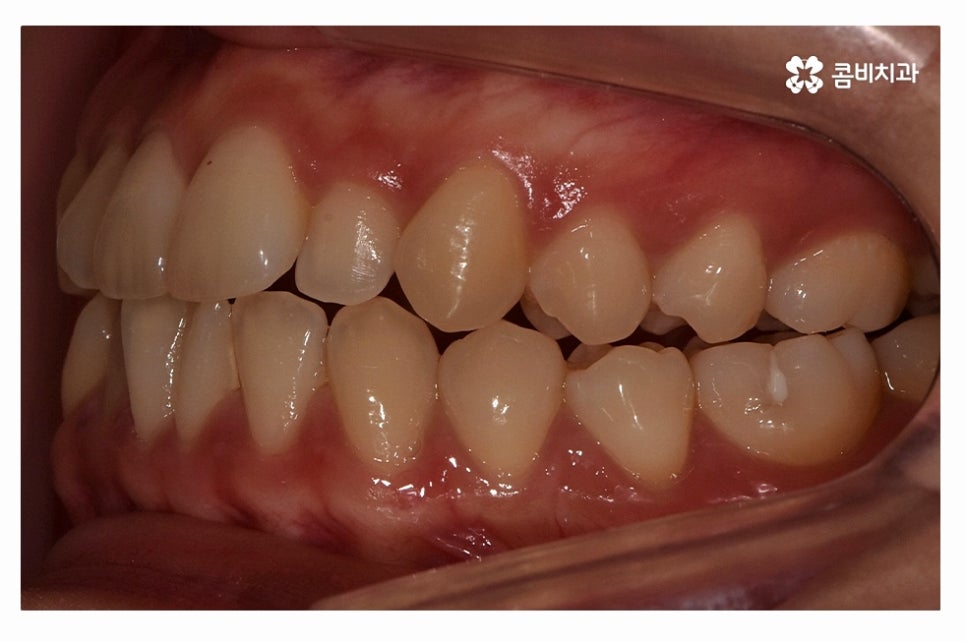

오늘 보여드릴 사례도 덧니교정이 비발치로 진행이 된 사례이며

치아의 이동 공간과 치아 상태, 골격, 얼굴형 등을

종합적으로 판단할 때 비발치로도 진행이 가능했던 사례라고 할 수 있어요.

위 환자분의 사례처럼 클리피씨교정이 보편적으로 많이 활용되고 있는데요.

클리피씨교정은 치아의 이동이 일반 장치에 비해 상대적으로

빠르기 때문에 치료 기간이 단축될 수 있으며

통증의 감소, 내원 횟수를 줄일 수 있다는 장점 등이 있어요.